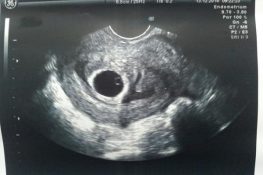

Que thử thai 2 vạch- chắc chắn của phụ nữ mang thai